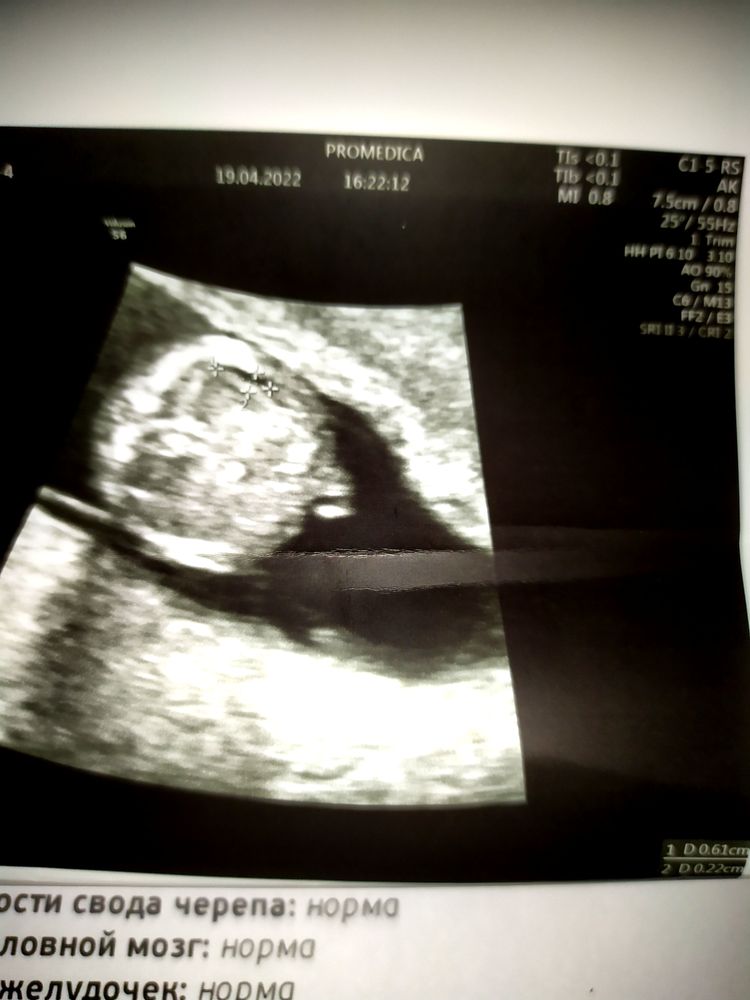

Ольга , спасибо большое за поддержку! В глубине души я надеюсь, что там всё формируется и мало ли что за полоска там могла образоваться, может органы увеличатся в размерах и вытеснят её. Не зря же скрининг делают с 11 до 13 недель, а у меня опережает и получается во все 14 поперлась